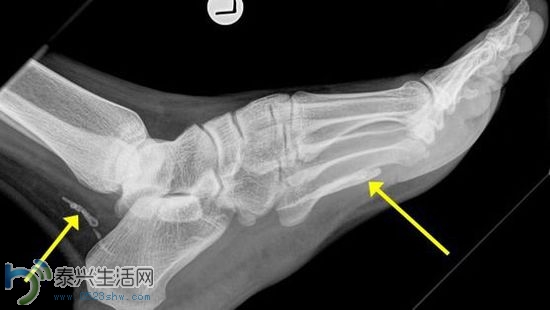

澳大利亚男子脚痛一年 手术取出两截寄生虫(图) |